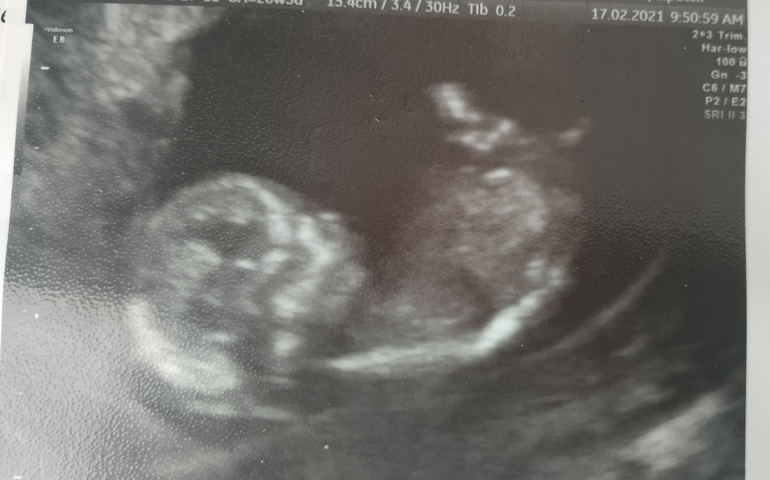

Первый скрининг + снимок

Сегодня состоялся первый скрининг. Ждала его с нетерпением, волновалась. Мы уже 6.4 см, всё в норме, сердцебиение 155 уд/м. Кувыркались и вертелись, показали маме всё, что можно, помахали двумя ладошками, переворачивались на оба бочка и на спинку))) прослезилась 🙈

Срок ПДР сместился на недельку (27.08)